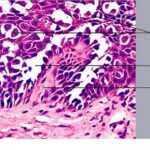

Histopathology. Although, as in Darier’s disease, early lesions may show small suprabasal separations, so-called lacunae, fully developed lesions show large separations, that is, vesicles and even bullae, in a predominantly suprabasal position . Villi, which are elongated papillae lined by a single layer of basal cells, protrude upward into the bulla, and in some cases, |

narrow strands of epidermal cells proliferate downward into the dermis. Many cells of the detached stratum malpighii show loss of their intercellular bridges; thus, acantholysis affects large portions of the epidermis. |

Individual cells and groups of cells usually are seen in large numbers in the bulla cavity. Despite the extensive loss of intercellular bridges, the cells of the detached epidermis in many places show only slight separation from one another, because a few intact intercellular bridges still hold them loosely together. This quite typical feature gives the detached epidermis the appearance of a dilapidated brick wall. |

Many of the cells of the stratum malpighii that have lost all or most of their intercellular bridges show a fairly normal cytoplasm and a normal nucleus in which mitotic activity has even been observed . Some of the acantholytic cells, however, have a homogenized cytoplasm, suggesting premature partial keratinization. In some instances, such acantholytic cells with premature keratinization resemble the grains of Darier’s disease. Occasionally, a few corps ronds are present in the granular layer . |